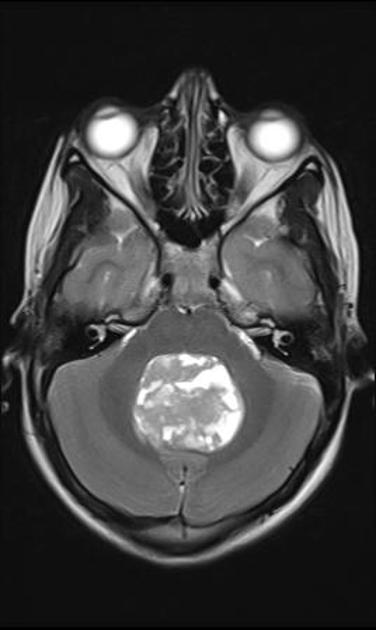

A comprehensive history and physical and MRI imaging of the CNS axis is required. The MRI typically shows a posterior fossa mass which is hypointense to iso-intense on T1 series. It is hyperintense (white) to white matter on T2 series. T1/gad shows heterogeneous enhancement and CT shows calcifications. Once the imaging series is obtained, CSF sampling (particularly in anaplastic Grade III) should be obtained to rule out leptomeningeal seeding. CSI may be required in anaplastic ependymoma.

Ependymoma T2

Ependymomas are the third most common pediatric CNS tumor. About half the cases occur in children under y. They can occor at any site in the ventricular system or spinal canal. In children, about 2/3 arise in the ependymal lining of the 4th ventricle. Tumors generally present with increased ICP. The tumor is usually large and well circumscribed, displacing, rather than invading structures. These tumors can and do extend through the foramen magnum into the upper cervical cord.